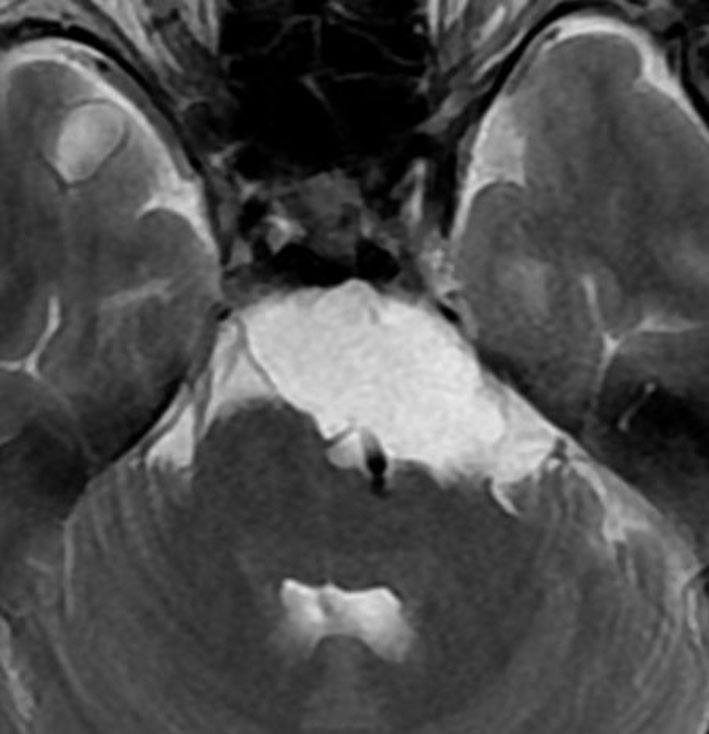

T2強調画像とFLAIR像です。FLAIRでは髄液より高信号となります。のう胞様の膨らみを有します。脊索腫と異なり,expanding mass と表現されます。

CISSとガドリニウム増強T1強調画像です。ガドリニウム増強されません。